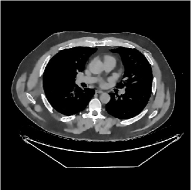

This section compares the reconstruction quality and runtime among the proposed MBIR method, PWLS-ST-, and other three MBIR methods, PWLS-EP, PWLS-DL, and PWLS-ST-. Table I shows that, for both 2D and 3D sparse-view CT reconstructions of the XCAT phantom, the proposed PWLS-ST- model outperforms PWLS-EP and PWLS-ST- in terms of RMSE. In addition, PWLS-ST- using a square transform (of size ) achieves lower RMSE than PWLS-DL using an overcomplete dictionary (of size ) for 2D sparse-view reconstructions. Fig. 3(a) and Fig. 4 show the reconstructed images for 2D and 3D phantom experiments, with different reconstruction models and different number of views. (See the corresponding error maps in the supplement.) The proposed PWLS-ST- consistently gives more accurate image reconstructions compared to other MBIR methods. Specifically, PWLS-ST- has smaller errors in the heart region (see zoom-ins in Fig. 3(a)) of 2D reconstructions than PWLS-DL and PWLS-ST-. In addition, compared to PWLS-ST-, PWLS-DL and PWLS-ST- have some ringing artifacts around the edges with high transition, e.g., edges between air and soft tissues. (See a comparison of profiles of PWLS-ST- and PWLS-ST- in the supplement.) In particular, PWLS-ST- and PWLS-DL give more visible ringing artifacts for 2D reconstruction from fewer views, and PWLS-ST- has these ringing artifacts for 3D reconstructions regardless of the number of views (see zoom-ins in Fig. 4). Table II reports runtimes of different MBIR methods in reconstructing the -views XCAT phantom scan. (FBPConvNet is a non-MBIR method and its runtime for processing a image is approximately one second with a TITAN Xp GPU.) While providing better reconstruction quality, the proposed Algorithm 1 of PWLS-ST- has shorter runtime compared to the algorithms of PWLS-DL and PWLS-ST- in Section III-A. Similar to the PWLS-EP algorithm, the reconstruction time of the PWLS-DL, PWLS-ST-, and PWLS-ST- algorithms can be further reduced by using ordered subsets [51].

Fig. 3(b) shows that when tested on the clinical scan data, the proposed PWLS-ST- method improves reconstruction quality in terms of noise and artifacts removal (e.g., see zoom-ins for soft-issue regions), and edge preservation (e.g., see zoom-ins for bone regions), compared to PWLS-EP and PWLS-ST-. Compared to PWLS-DL, PWLS-ST- achieves comparable image quality, but requires less computational complexity.

| (a) 2D fan-beam CT experiments |